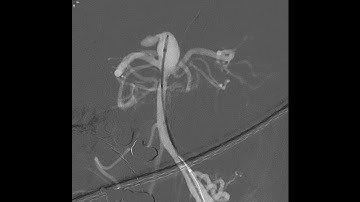

The CLEVER Study – WEB 17 for Ruptured and Unruptured Aneurysms